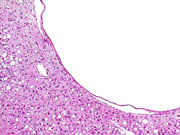

Bile duct cyst. A solitary biliary cyst at the edge of a liver lobe. This was grossly visible and such cysts are typically filled with clear to straw colored fluid and lined by flattened biliary epithelium. They are found occasionally in the liver of untreated mice. Note: The clear space in the cytoplasm of the hepatocytes was previously occupied by glycogen which has dissolved out in the aqueous formalin fixative.